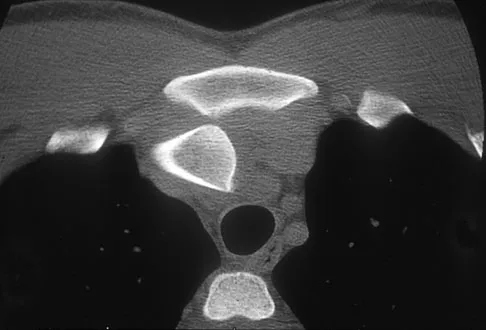

A 47-year-old woman has had a 1-month history of left hip and medial thigh pain that is exacerbated by sitting. Laboratory studies show a total protein level of 8.2 g/dL (normal 6.0 to 8.0) and an immunoglobulin G (IGG) level of 2,130 mg/dL (normal 562 to 1,835). A radiograph, CT scan, and biopsy specimen are shown in Figures 38a through 38c. What is the most likely diagnosis?

Explanation

The laboratory studies and histology are both consistent with myeloma. Infection should show white blood cells other than plasma cells on histology. Lymphoma would show lymphocytes, not plasma cells. The lack of bone formation on the imaging studies and the lack of osteoid on histology rule out osteosarcoma. The cells have too much cytoplasm and nuclear chromatin to be Ewing's sarcoma cells.